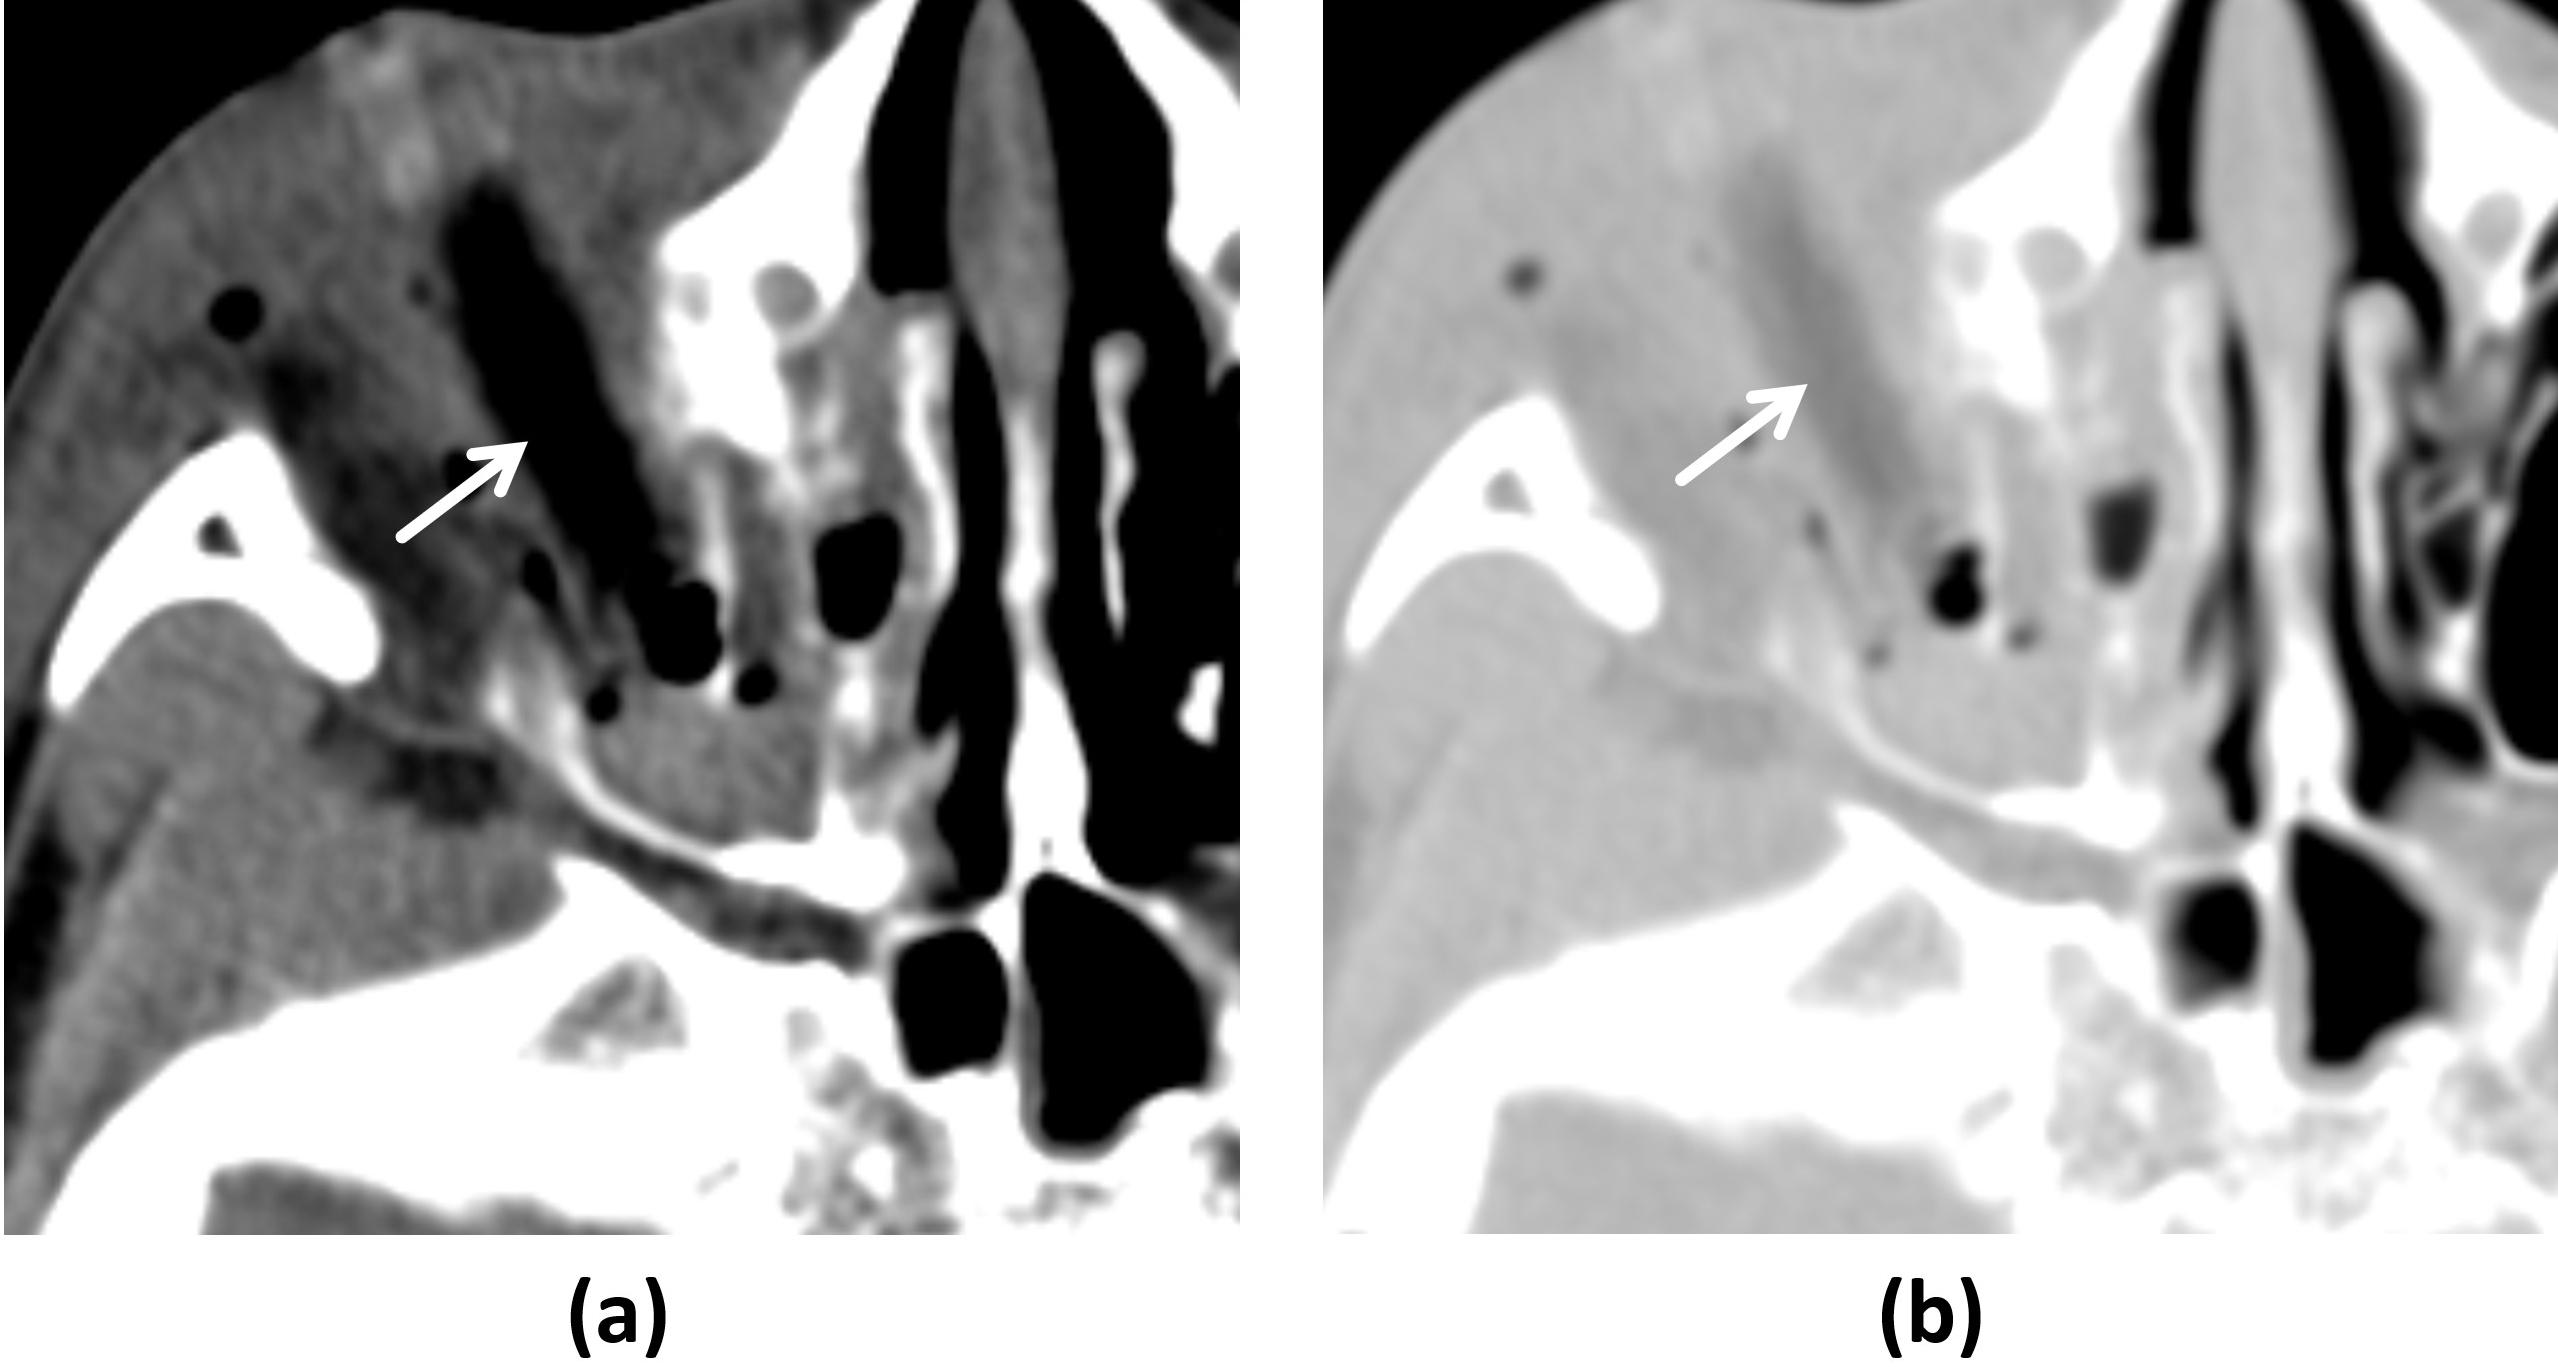

Three days after she was admitted to the hospital, a new medical team took over and noticed the woman had noisy breathing, which occurs with obstructed air flow. The team reexamined the previously obtained chest x-ray and brain and chest CT scans. The images revealed a large foreign body in the woman's hypopharynx-upper esophagus. The object was not described in the report initially read by junior radiology residents.

The patient failed a swallow study, and images were acquired of her neck soft tissue and anterior-posterior cervical spine, which revealed a 5.4 x 2.3 x 4.3-cm foreign body lodged in her hypopharynx anterior to the C3-C6 vertebrae, the authors wrote.